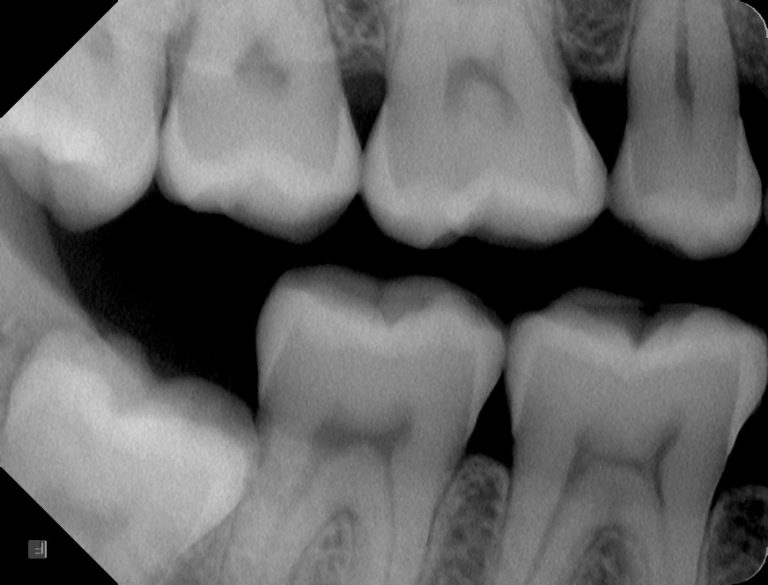

Lokalni posnetek

Intraoralne tehnike posnetkov razdelimo na tehniko zagriza ali ang. bitewing in periapikalno tehniko.

Bitewing slikanje zobnih kron

Bitewing slikanje zob je tehnika, ki se uporablja za prikaz zobnih kron.